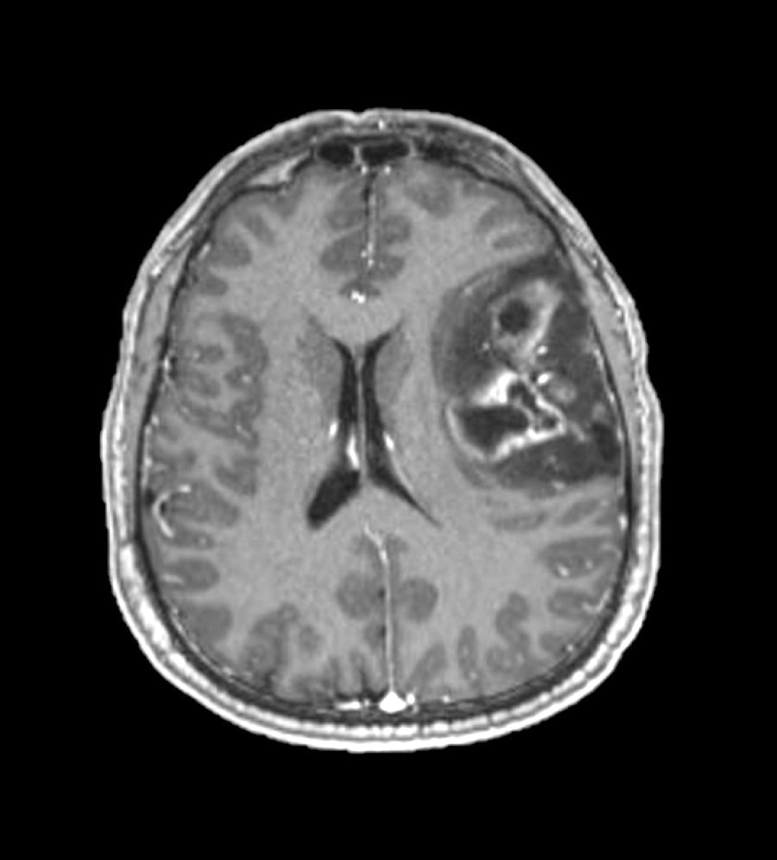

Radiology images

Radiology description

- CT:

- Expanding, intra-axial, poorly defined mass of low density

- Variable calcification may be seen

- Contrast enhancement and central hypodensity due to necrosis, occur with higher grades

- MRI:

- T1 hypodensity and T2 hyperintensity

- T2 hyperintensity with relative FLAIR sequence hypointensity (T2 FLAIR mismatch) is a relatively suggestive indication of IDH mutant astrocytoma (Clin Cancer Res 2017;23:6078)

- Distortion and enlargement of involved areas, including associated cortical ribbon

- Contrast enhancement is typically present in higher grade tumors (J Neurooncol 2019;141:327)

- Ring-like enhancement around central necrosis typical of grade 4